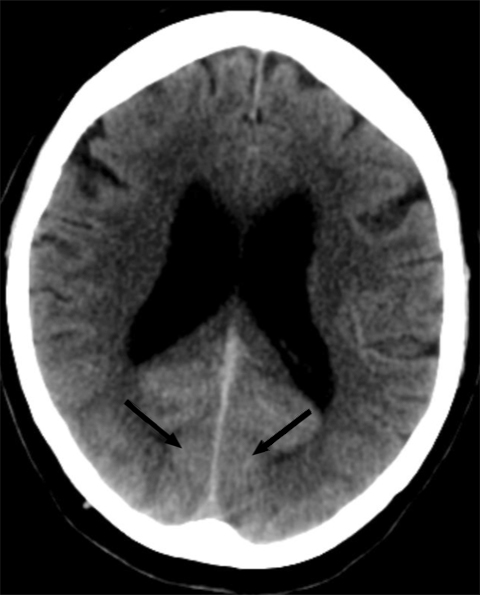

30 minutter etter at hun ble akutt blind, ble det tatt CT caput og CT-angiografi av intrakraniale arterier. CT caput viste utbredt diffus kontrastoppladning i synsbarken (oksipitalt) bilateralt, men ingen blødning eller infarkt (figur 1). CT-angiografi viste ingen karokklusjon eller karspasmer. Som forventet ved en kranial dural arteriovenøs fistel var det økte kartegninger og arterialisert kontrastfylning i durale vener.

På pasientens CT-bilder var det retensjon av kontrast i synsbarken på begge sider. CT-bildene var gjort uten kontrast, så den synlige kontrasten måtte være fra konvensjonell cerebral angiografi gjort to timer tidligere. CT-angiografi viste åpne kar. På MR var det ingen nytilkomne signalforandringer. De kliniske symptomene sammen med bildefunnene passet dermed ikke med cerebral iskemi på bakgrunn av tromboembolisme eller karspasmer.

Dette er en eksklusjonsdiagnose. MR caput og eventuelt CT caput med CT-angiografi er indisert for å utelukke blødning eller iskemisk årsak til synsaffeksjon. MR kan være negativ eller vise høysignal på T2- og FLAIR-signaler som ved vasogent ødem. CT kan vise normale funn eller kontrastoppladning oksipitalt. CT-angiografi fremstiller åpne kar uten spasmer.